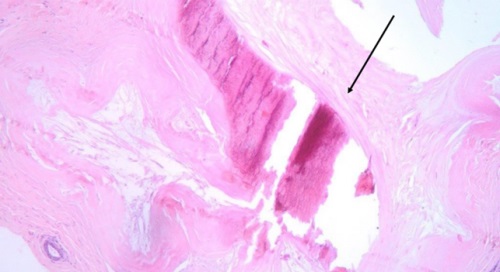

I ricercatori hanno scoperto, infatti, che la relazione tra le microcalcificazioni e il tumore è legata alla presenza di un particolare minerale chiamato whitlockite, che è ricco di magnesio e che si trova nelle microcalcificazioni solo in assenza del tumore. I ricercatori hanno usato tecniche avanzate di spettroscopia (Raman, WAXS, XRF), per analizzare le microcalcificazioni prelevate da pazienti affette da tumore al seno. Hanno confrontato i campioni con quelli di donne sane e hanno osservato che nei tessuti tumorali la whitlockite era quasi assente, mentre nei tessuti sani era abbondante.

Questo suggerisce che il tumore al seno ha la capacità di alterare il metabolismo del calcio e del magnesio nel tessuto mammario, influenzando la formazione delle microcalcificazioni, eliminando la whitlockite e rendendole più dure, cosa che le rende in grado di stimolare ancora di più la crescita del tumore.